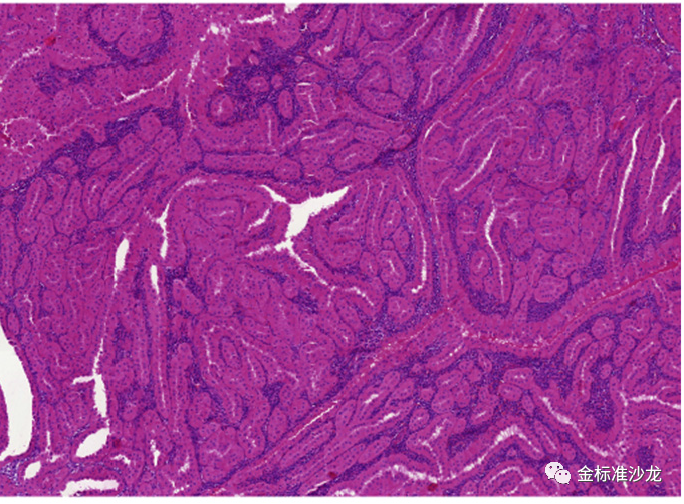

因常存在乳头状或管状乳头状癌区域和高级核特征,包括过去常被错误诊断为2型pRCC的还包括MiTF家族(包括TFE3重排的和TFEB重排的RCC和TFEB扩增RCC,图2,3),新的实体嗜酸性实体和囊性(ESC)-肾细胞癌,管状囊性肾细胞癌和集合管癌。另一个实体粘液管状和梭形细胞癌由于具有不同的染色体改变和Hippo通路肿瘤抑制基因的双等位基因失调,已独立于1型pRCC,尽管二者存在形态及免疫组化重叠。

图2 TFE3重排RCC可见乳头状的结构,高级别核特征,细胞淡染或嗜酸,类似于2型pRCC。免疫组化提示TFE3弥漫强阳性表达